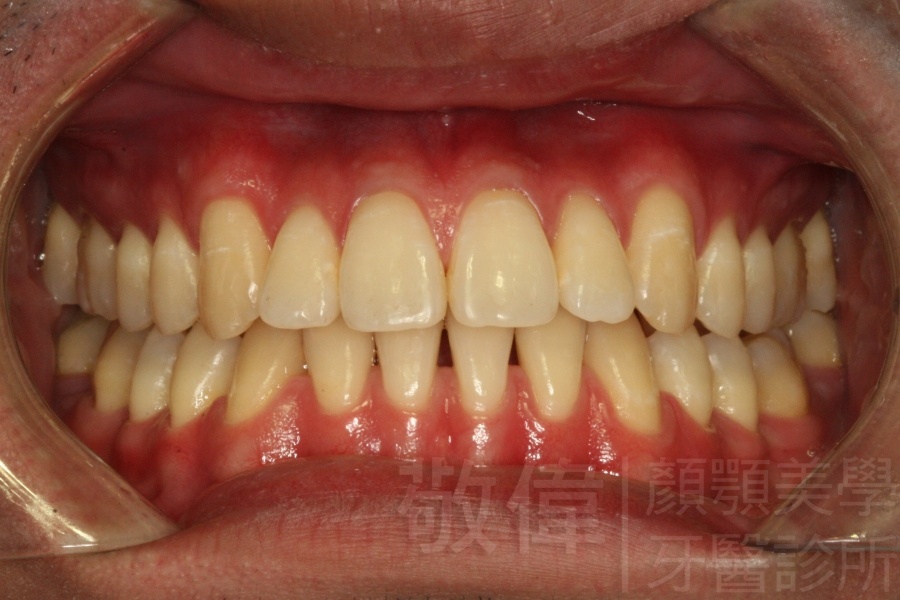

變臉矯正,原來戽斗妹跟大歪臉變成自信正妹

因為矯正與正顎手術的配合,使「戽斗妹」變成了「陽光正妹」,完全的改變了她的人生,在面對各種場合、與人交際都散發出自信微笑。所以,奉勸家長,如果小朋友有臉顎畸型的問題,應該考慮配合做這種簡單、安全、有效的正顎手術。

「3D齒顎顏矯正」,不止矯正您的牙齒,也會改變您的人生。「治療前」和「治療後」出社會的人生際遇一定會截然不同。